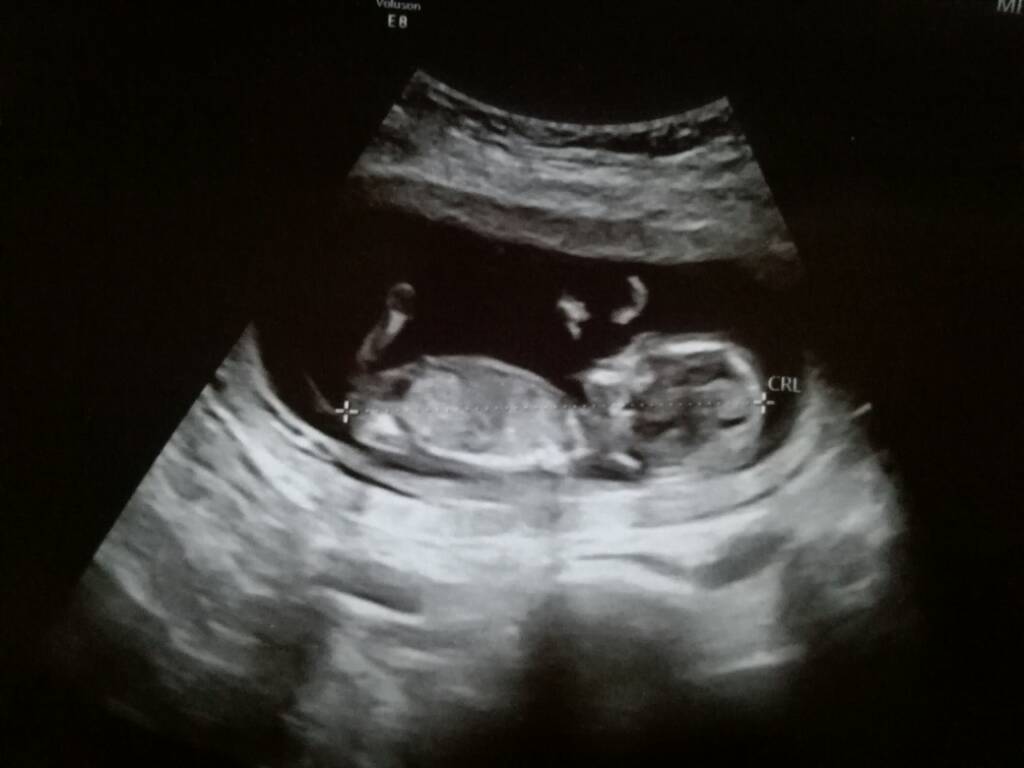

No dobra i ja po wizycie. Prawie zeszłam na zawał do tej 15, na wizycie u położnej wyszło mi ciśnienie 159:110!!! Bo mi jeszcze w trakcie pomiaru zaczęła komentować moje zapiski z pomiarami ciśnienia że słabizna i że się jej nie podobająwięc się zdenerwowałam i od razu mi skoczyło. Ale na szczęście wszystko dobrze

dzieciaczki się ruszały!! Super widok, prenatalne jednak za tydzień w poniedziałek rano bo powiedział że będzie lepiej widać i musi mieć więcej czasu na dwójkę.

Ciąża zdecydowanie jednokosmówkowa i w związku z tym mam na siebie uważać, więc mój wylot do Barcelony w listopadzie odpływa w siną dal... Ale jeśli tak ma być bezpieczniej to trudno, pojadę innym razem.

Dzidki mają po pięć i pół cm, na razie idą łeb w łeb. Tętno 160 oba, więc też super. Więcej dowiem się za tydzień. Wszystkich co się martwią brakiem objawów niniejszym uspokajam że nic to nie znaczy

Zwolnienie zaproponował ale nie chcę jeszcze. Muszę pozamykać projekty, najwyżej będę pracować z domku. Nn ile mam ładnych ujęć z dziś ale jedno wrzucam chociaż powiem szczerze że taka że mnie specjalistka że nie wiem czy to po lewej to głowa i ręce czy pupa i nogiufff ale zeszło że mnie ciśnienie